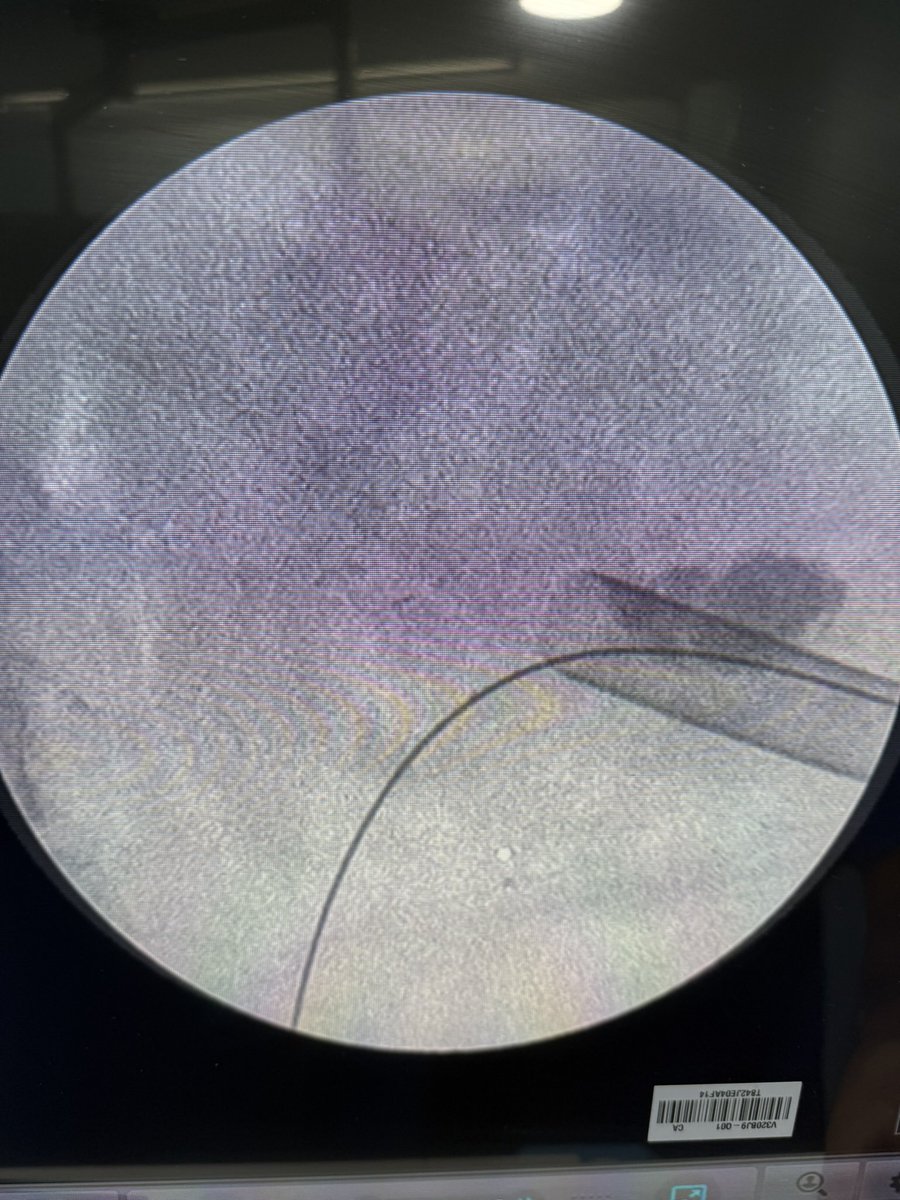

💥 Our Hands-On Course on Ultrasound-Guided PCNL at @CMUN_Urologia was a great success!

An incredible day of practical learning, experience sharing, and passion for advancing minimally invasive surgery